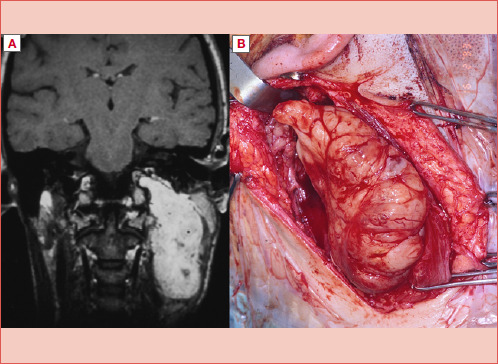

目的:探讨显微外科入路治疗咽旁间隙(PPS)肿瘤的安全性和有效性。第二个目的是评估术前和术后最终组织病理学诊断之间的对应关系。方法:对1985年至2022年间在2个三级转诊中心采用显微外科颈腮腺入路治疗的连续系列原发性PPS肿瘤进行分析。样本包括94例患者的97个肿瘤(88个良性和9个恶性),其中11例在我们中心首次诊断时患有复发性肿瘤。手术入路,根据假定的术前诊断,是包膜和整体切除(包括保守或根治性切除PPS)。结果:在97个肿瘤中,有88个肿瘤被完全切除。PPS显微手术后复发8例(多形性腺瘤4例,恶性神经鞘瘤2例,黑色素瘤1例,血管外皮细胞瘤1例)。8例复发病例中有4例在我们中心首次发现时是复发病例。术前诊断与最终组织学完全一致只发生在良性病变组,如副神经节瘤、神经鞘瘤或脂肪瘤,并行包膜切除。结论:显微外科手术可以通过狭窄的手术通道增加手术空间,改善对关键切割面、血管和神经的剥离,并允许显露病变的尾侧和颅侧范围,从而支持经颈腮腺入路。在我们的研究中,包膜和整体切除PPS对大多数患者都是有效的。在高级别恶性肿瘤中,除PPS壁外更广泛切除的病变可能包括血管和神经,应准确平衡适应证。

Objective: To investigate safety and efficacy of the microsurgical approach to parapharyngeal space (PPS) tumour. A secondary goal was to evaluate the correspondence between preoperative and final histopathologic diagnosis after surgery.

Methods: A consecutive series of primary PPS tumours treated between 1985 and 2022 in 2 tertiary referral centres with a microsurgical cervico-parotid approach was considered. The sample included 97 tumours (88 benign and 9 malignant) in 94 patients, of which 11 affected by recurrent tumours when first diagnosed at our centres. The surgical approaches, planned on the presumptive preoperative diagnosis, were pericapsular and en bloc resections (including either conservative or radical resections of the PPS).

Results: Pericapsular and en bloc resections of the PPS achieved complete removal in 88 out of 97 tumours. Relapses after PPS microsurgery occurred only in 8 cases (4 pleomorphic adenomas, 2 malignant schwannomas, one melanoma, and one haemangiopericytoma). Four of the 8 relapsed cases were recurrent cases when first seen at our centres. A complete correspondence between preoperative diagnosis and final histology occurred only in the group of benign lesions classified as paraganglioma, schwannoma, or lipoma, submitted to pericapsular resection.

Conclusions: Microsurgery may support the transcervical-parotid approach, by enhancing the operative space through narrow surgical corridors, improving dissection on critical cleavage planes, vessels and nerves, and allowing the exposure of both caudal and cranial extent of the lesions. In our series, pericapsular and en bloc resections of the PPS were effective in most of the included patients. In high-grade malignancies, where the morbidity of a wider resection beyond the PPS walls may include vessels and nerves, the indication should be accurately balanced.